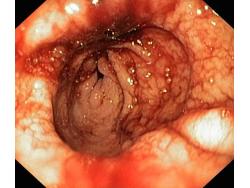

Krwawienie